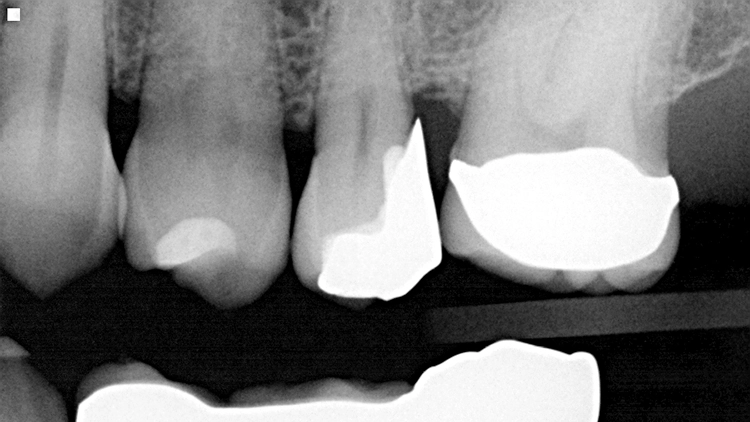

Die weitere Versorgung der Kavität erfolgte analog zu Fall 1 nach Anwendung eines klassischen Etch&Rinse-Mehrflaschenadhäsivs und schichtweiser Applikation und Polymerisation von Venus Diamond ONE (Kulzer) mit einem Hochleistungs-LED-Polymerisationsgerät > 1.000 mW/cm2 für jeweils 20 Sekunden Lediglich anstelle des Venus Diamond Flow Baseliners kam aufgrund der sehr hohen ästhetischen Ansprüche des Patienten Venus Diamond Flow in der Farbe A2 zum Einsatz – der Patient hätte keinen weiß-opaken Rand an seiner Restauration akzeptiert. Das Ergebnis (Abb. 9) überzeugte den Patienten nicht nur funktionell, sondern vorrangig ästhetisch: Auch hier passt sich die Universalfarbe perfekt an die Zahnhartsubstanz an. Zur Überprüfung der Ausdehnung der Überkappung wurde im Anschluss an die Versorgung eine Zahnfilm-Röntgenaufnahme erstellt (Abb. 10).

Das Bild zeigt den perfekten Randschluss der Restauration in Kombination aus Venus Diamond Flow A2 und Venus Diamond ONE. Beeindruckend ist zudem die sehr hohe Röntgenopazität des Materials. Das pulpanahe, weniger röntgenopake Material ist das TheraCal LC-Überkappungsmaterial.